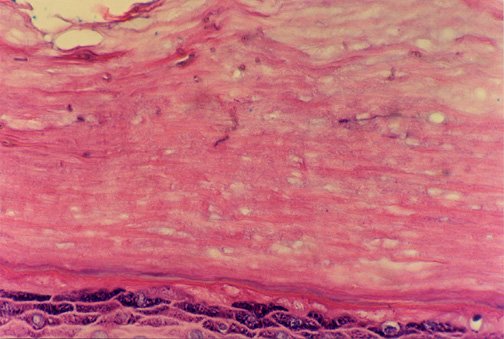

DERMATOHISTOPATHOLOGY:

High power depicting inconspicuous hyperpigmented hyphae within the stratum corneum. (H+E stain, 400x)